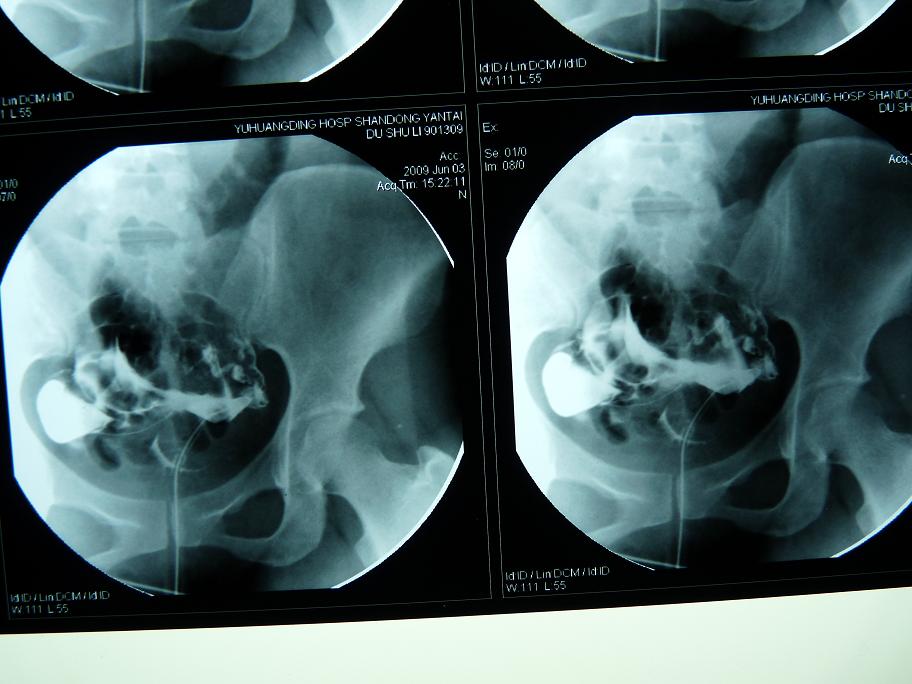

以下是引用黑白光影在2009-6-6 9:58:00的发言:[br]左侧输卵管粗细不均、僵硬、通而不畅,右侧输卵积水。